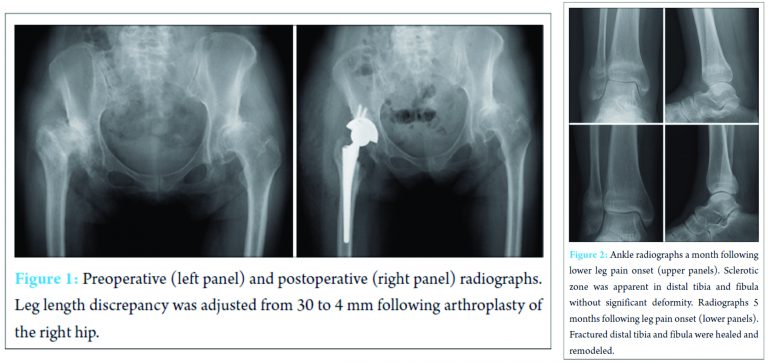

A 54-year-old woman presented with severe pain in the bilateral hip joints. She was limping with a T-cane, and her activities of daily living were remarkably limited. Her height, weight, and body mass index were 152 cm, 55 kg, and 23.8 kg/m2, respectively. The Japanese Orthopaedic Association hip Score was 54 on the right and 45 on the left. Plain radiographs showed bilateral loss of joint space, large osteophytes, and marked deformity of the femoral head and acetabulum (Fig. 1). The width of the cortex of her right femur shaft was thinner than that on her left side. Her right lower limb was 30 mm shorter than her left limb. She was diagnosed with end-stage osteoarthritis of the bilateral hip joints. She first underwent THA on the right side, and it was performed successfully (Fig. 1). The leg length discrepancy was improved by 4 mm after the surgery; however, the right side was still shorter than the left. Full weight bearing was initiated on the second postoperative day. Overall, the postoperative course was uneventful and her walking ability improved.

Twenty-two weeks after the surgery, she suddenly experienced severe pain and swelling in the right leg without any history of trauma. She visited her local doctor first and was diagnosed with cellulitis. Although she was treated with oral antibiotics, her symptoms persisted. One month later, she visited our hospital again in a wheelchair. Her right distal leg and ankle were diffusely swollen, red, warm, and tender. Her body temperature was 36.8°C. The following laboratory data were collected, showing normal range in parentheses: White blood cell count, 5300/μl (neutrophil 63.3%; 4000-8000/μl); erythrocyte sedimentation rate, 18 mm/h (1-15 mm/h); C-reactive protein, 1.08 mg/dl (0-0.4 mg/dl); uric acid, 4.7 mg/dl (2.0-6.0 mg/dl); tartrate-resistant acid phosphatase 5b, 478 mU/dl (premenopausal normal range, 120-420 mU/dl); bone alkaline phosphatase, 31.0 μg/l (premenopausal normal range, 2.9‑14.5; postmenopausal normal range, 3.8-22.6 μg/l); calcium, 9.1 mg/dl (8.4‑10.3 mg/dl); and inorganic phosphorus, 3.5 mg/dl (2.3-4.2 mg/dl). Plain radiographs revealed a sclerotic linear zone in the distal tibia and fibula without significant deformity (Fig. 2). There was no arthritic change in the ankle joint. Dual X-ray absorptiometry of the lumbar vertebra was performed to evaluate osteoporosis. Her bone mineral density was 0.731 g/cm2, T-score was −2.5, and Z-score was −0.9. She was diagnosed with an insufficiency fracture in the distal tibia and fibula following THA. Her right leg and ankle were immobilized with a U-slab plaster splint for another 4 weeks. She was advised to bear weight as tolerated. Her symptoms subsided gradually, and fracture union was confirmed on the follow-up X-ray. She was also instructed rehabilitation to prevent osteoporosis.